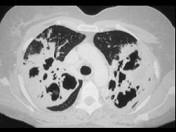

问题 一养鸽女,48岁,发热,咳嗽,咳浓痰带血半月余,请结合CT,选出最可能的诊断 ( )

选项 A.原发性肺结核 B.肺曲菌病 C.肺癌 D.间质性肺炎 E.支气管扩张

答案 B